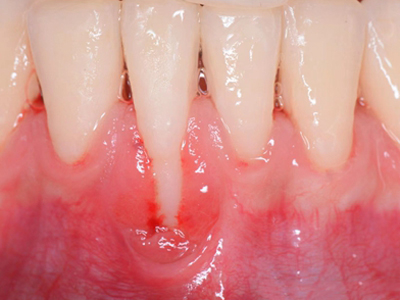

牙龈退缩多处牙龈萎缩出血图

牙龈退缩严重时,上排牙有多颗牙齿的牙龈部位发生退缩,导致牙根暴露,同时牙龈处还有出血的症状,伴有疼痛感,建议及时前往医院通过手术等手段进行治疗。